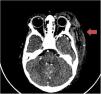

Presentamos el caso de un niño de 16 meses que consulta por aparición hace 8 horas de placa purpuroequimótica parietooccipital izquierda que se extiende hasta párpado y pabellón auricular (fig. 1 A.). Niegan traumatismo. Refieren infección de vías respiratorias altas. Afebril, buen estado general, sin hematomas, petequias ni equimosis en otras localizaciones. En la analítica destaca trombocitopenia (49.000/μl) y coagulopatía grave con ausencia de coagulación, indetectable y dímero D de 976mg/l. No signos de malignidad o hemólisis. Leucocitosis con neutrofilia con mínima elevación de reactantes de fase aguda. Radiografía de tórax con infiltrado perihiliar bilateral inespecífico. Ecografía doppler de la lesión y tomografía computarizada (TC) craneal que confirman cefalohematoma extraaxial sin hemorragia intracraneal ni trombosis asociadas.

Ante dichos hallazgos, se administran vitamina K, fibrinógeno, plasma fresco congelado (PFC) y transfusión de plaquetas con posterior normalización de la coagulación, asociando tratamiento antibiótico con cefotaxima y azitromicina. Estudios etiológicos infecciosos negativos, excepto PCR positiva de rinovirus en aspirado nasofaríngeo. A las 24 h se realizan angio-TC de control (fig. 2) y angiorresonancia magnética cerebral con estabilidad de la lesión. Se amplía estudio etiológico con factores de coagulación normales, test de Coombs directo C3 positivo débil, antitrombina III y ADAMTS-13 normales. Destaca disminución de la proteína C (PC) del 28% y disminución de la proteína S (PS) del 6,5%. Orientándose como púrpura fulminante asociada a deficiencia de PS, se inicia tratamiento con inmunoglobulinas, corticoides y PFC. A las 48 h presenta trombosis parcial de la vena braquial derecha secundaria a catéter central de inserción periférica recibiendo tratamiento con heparina. Aumento progresivo de los niveles de PS hasta su normalización a las 48 h. Estudio familiar con PS normal. Confirmación de diagnóstico ante la positividad de anticuerpos anti-PS. Se encontró en madre y paciente mutación heterogénea del factor V de Leiden. Debido a evolución a placa necrótica, requirió desbridamiento quirúrgico a las 3 semanas (fig. 1 B) y oxigenoterapia hiperbárica los meses posteriores para mejorar la cicatrización (fig. 1 C).